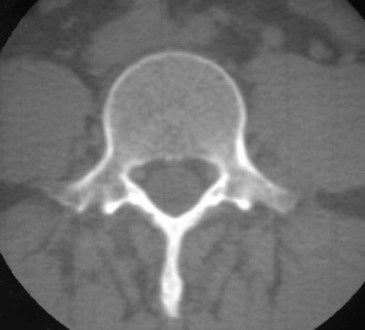

Cuando revisamos la columna lumbar de un paciente en una TC, cada vértebra debe tener al menos un corte en que se vea un anillo vertebral completo, formado por el cuerpo por delante, los pedículos y las láminas a los lados y, cerrando en la parte posterior, la base de las apófisis espinosas.

Sin embargo, la rotura de la pars interarticularis (espondilolisis) provoca una interrupción del anillo vertebral, separando los elementos posteriores de las masas laterales. La imagen corresponde a un anillo incompleto por espondilolisis bilateral (flechas). No debe confundirse esta imagen con las articulaciones interapofisarias, situadas por encima (las de L4-L5) y por debajo (L5-S1) de este plano.

Esta imagen corresponde al plano del anillo completo.